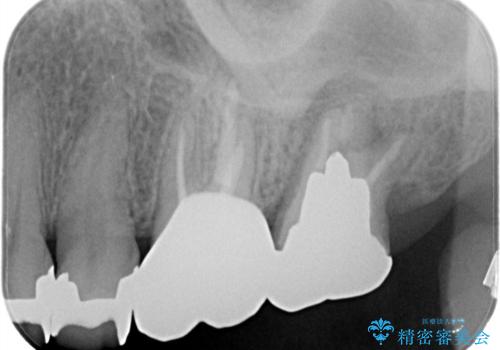

【再根管治療】オールセラミッククラウンによる修復

- 治療途中の歯があることを主訴に来院されました。

根管治療を行なったのちオールセラミックにて修復治療を行なっております。

第二大臼歯の治療は希望されませんでした。